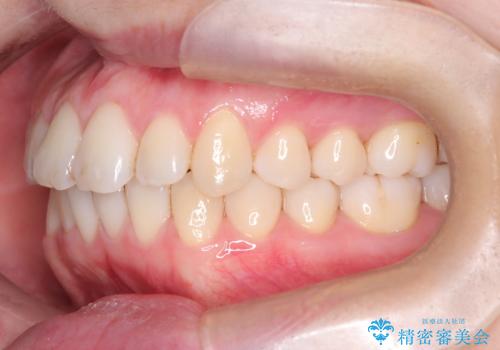

前歯の傾きが改善され、横顔の印象が大きく変化。上下の正中も一致し、かみ合わせのバランス(臼歯関係)も整いました。目立たず快適に治療ができた点にもご満足いただき、「人に気づかれずにここまで変化できるとは思わなかった」とのお声をいただいています。治療後はリテーナーを用いて、仕上がりをしっかり保っています。

インビザラインでも、TADを併用することでより精密な歯の移動が可能になります。